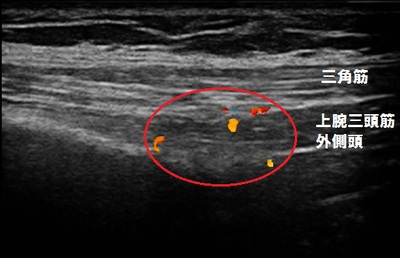

右肩前外側部 超音波長軸像

だんだん痛みが強くなったので当院に来院されました。超音波検査を実施したところ、右肩関節の

前外側部の三角筋と上腕三頭筋外側頭が強く引き伸ばされ損傷し、炎症(痛み、腫れ)が起きている

様子が認められました。